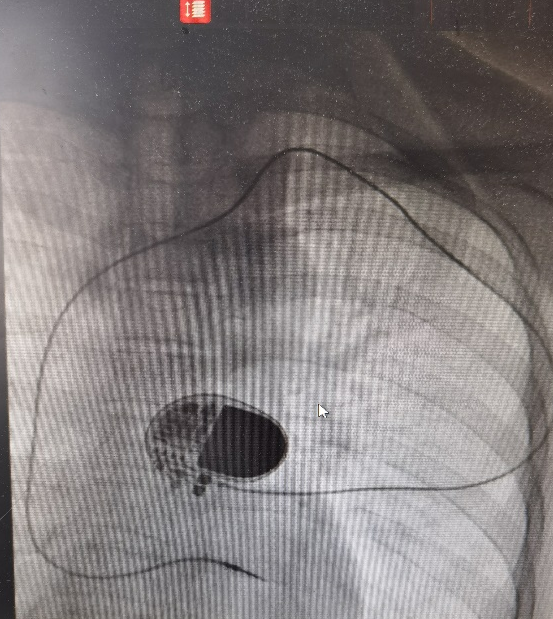

怎么办?湖州市中心医院心内科主任卢孔杰经过反复考虑,决定采取一种特殊的临时起搏方案——临时永久起搏治疗,即通过腋静脉通道插入永久起搏螺旋电极到右心室,外接尚有电量的脉冲发生器,这样不仅电极固定更牢固,而且能保持术中供电稳定。手术顺利,术中患者心率稳定于 60 次/分。病理结果也显示该占位为良性。

第一关过了,接下来则要考虑植入永久起搏器来稳定心率。但新的难题又出现了:患者极瘦,身高 180 cm,体重却不到 100 斤,而且胸部皮肤菲薄。这种状态下,常规的永久起搏器植入方式很容易出现起搏囊袋感染及溃破。而且患者有智力障碍,容易因为植入侧手臂活动不受限制,造成起搏器电极脱位现象,一旦如此后果不堪设想。